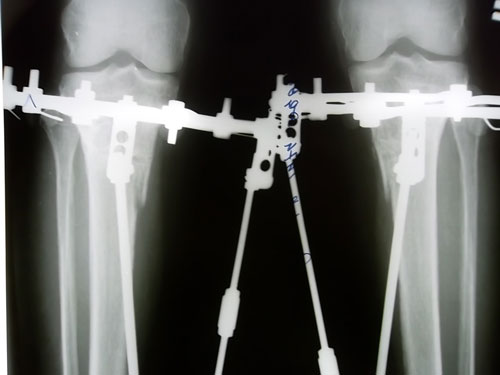

Рентгеновские снимки в день снятия аппаратов.

Дата операции 14.08.2012г.

Дата снятия аппаратов 15.11.2012г.

Срок лечения 90 дней.